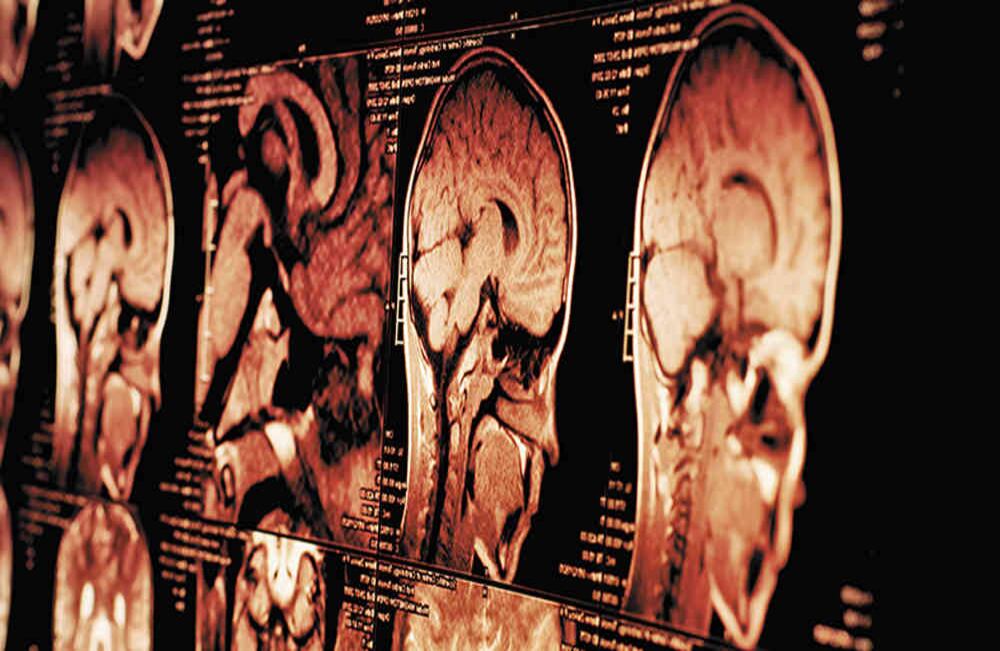

La tomografía computarizada permite tomar imágenes desde diferentes ángulos para crear vistas tridimensionales de tejidos y órganos.

El médico Raymond Damadian demostró en 1971 la efectividad de la resonancia magnética para detectar enfermedades. Esta es una técnica vigente.